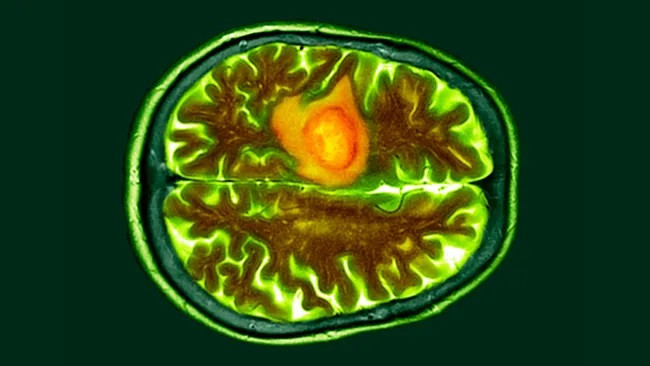

| Glioblastomas là dạng ung thư não nguy hiểm nhất. Một trong những khối u này được hiển thị trong hình ảnh quét não có màu cam. (Ảnh: DR P. MARAZZI) |

Theo hai thử nghiệm lâm sàng ban đầu, một phương pháp điều trị dựa trên tế bào miễn dịch mới đối với u nguyên bào thần kinh đệm, loại ung thư não nguy hiểm nhất, đã cho thấy nhiều hứa hẹn trong việc thu nhỏ khối u trong thời gian ngắn.